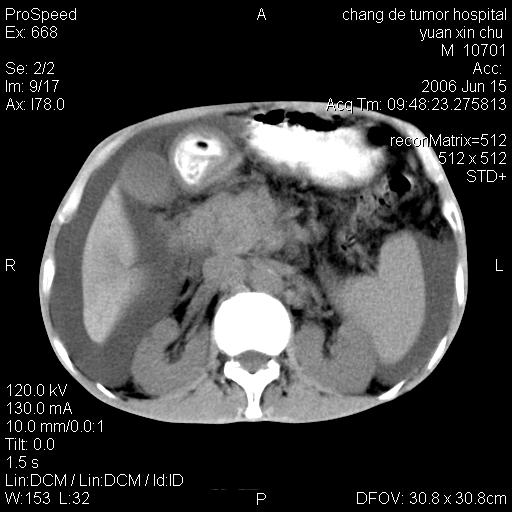

以下是引用qian在2007-4-23 19:06:00的发言:[br]胰腺体积增大,轮廓欠规则,肝轮廓波浪状改变,肝裂增宽,肝周、脾周有液性密度,腹膜后肿大淋巴结,考虑1、胰腺癌伴腹膜后淋巴结转移;2、肝硬化伴腹水。

以下是引用卜一在2007-4-23 20:12:00的发言:[br]胰腺体积增大,轮廓欠规则,肝轮廓波浪状改变,肝裂增宽,肝周、脾周有液性密度,腹膜后肿大淋巴结,考虑1、胰腺癌伴腹膜后淋巴结转移;2、肝硬化伴腹水。支持!